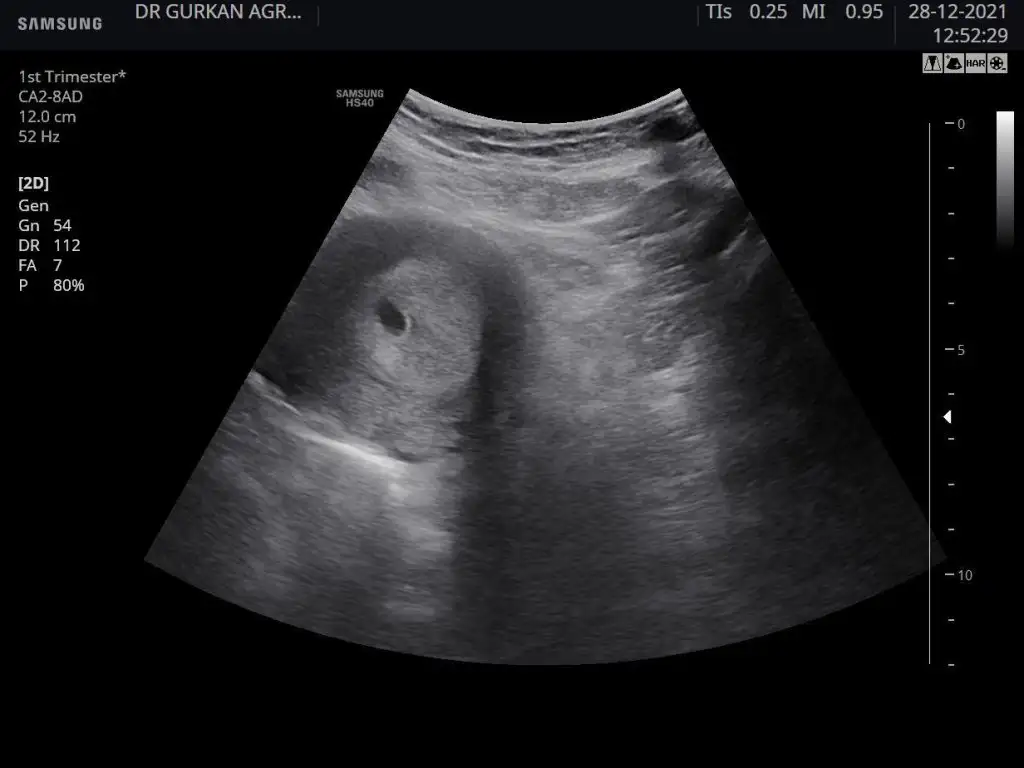

Kızlar bu bebiş doğdu eski usg si bu karından çekildi sizce kızmı erkek mi. Bakalım ramzi tutuacakmı

Eklentiler

• 0DCEF50D-ACE6-4185-8097-6F4BE314F73F.webp

41,6 KB · Görüntüleme: 74

• F171D4CC-1C2D-471D-8781-B2D9429E59F7.webp

21,8 KB · Görüntüleme: 79

• 14C4C8ED-DA59-4461-A23B-D4F4C45BBCF8.webp

22,9 KB · Görüntüleme: 70